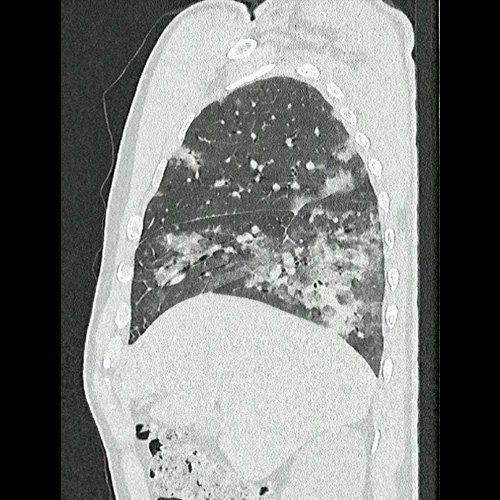

- Tomografía de tórax sin contraste endovenoso (Dia 0):Se observan múltiples áreas de consolidación parenquimatosa con broncograma aéreo y de distribución difusa por ambos pulmones, predominando en los lóbulos inferiores, asociadas a engrosamiento de los septos y rodeadas de tenue vidrio esmerilado. Se identifican estructuras ganglionares lateroaórticas, pretraqueales y subcarinales, ninguna de ellas sin alcanzar rango megálico.

Tomografía de tórax sin contraste endovenosos (Ventana pulmonar- corte sagital)

Tomografía de tórax sin contraste endovenosos (Ventana pulmonar- corte sagital)

Tomografía de tórax sin contraste endovenosos (Ventana pulmonar- corte sagital)